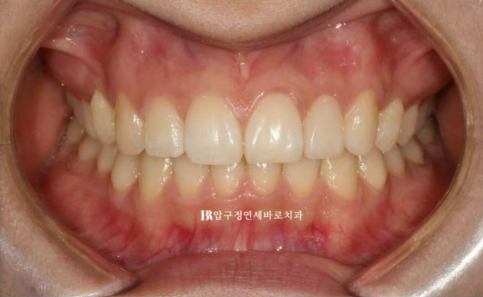

23.10~24.05

교합이 떠 있던 작은어금니도 제자리를 찾았습니다.

앞니가 깊게 물리는 과개교합도 어느정도 해결이 되었습니다.

중심선 개선도 눈에 띕니다.

앞니 교정으로 이 많은 것들이 좋아졌습니다.

미소는 자연스럽게 개선이 됩니다.